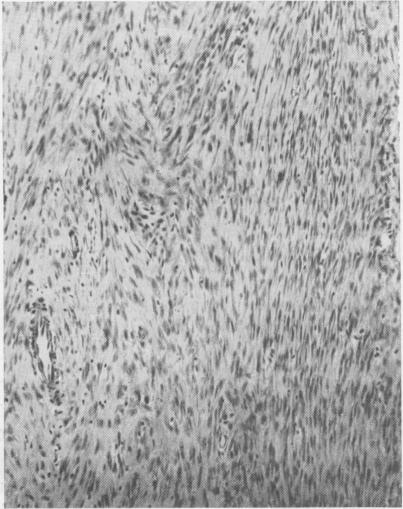

Desmoid tumors particularly as related to their surgical removal.

Ann Surg. 1954 Mar;139(3):335-40. doi: 10.1097/00000658-195403000-00011.